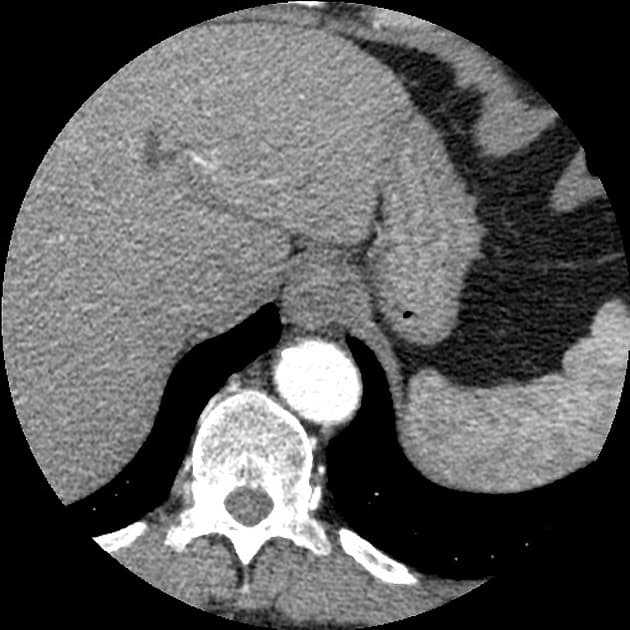

- Một tổn thương dạng khối giới hạn không rõ (ill-defined), tăng quang kém, kích thước 25mm, ở phân đoạn gan thứ 6. Ngoài ra, hai khối nhỏ hơn, kích thước 15mm và 7mm, được quan sát thấy ở phân đoạn gan thứ 7. Tất cả các tổn thương nêu trên đều trở nên đồng tỷ trọng (isodense) so với nhu mô gan xung quanh trên các hình ảnh pha trễ (delayed images).